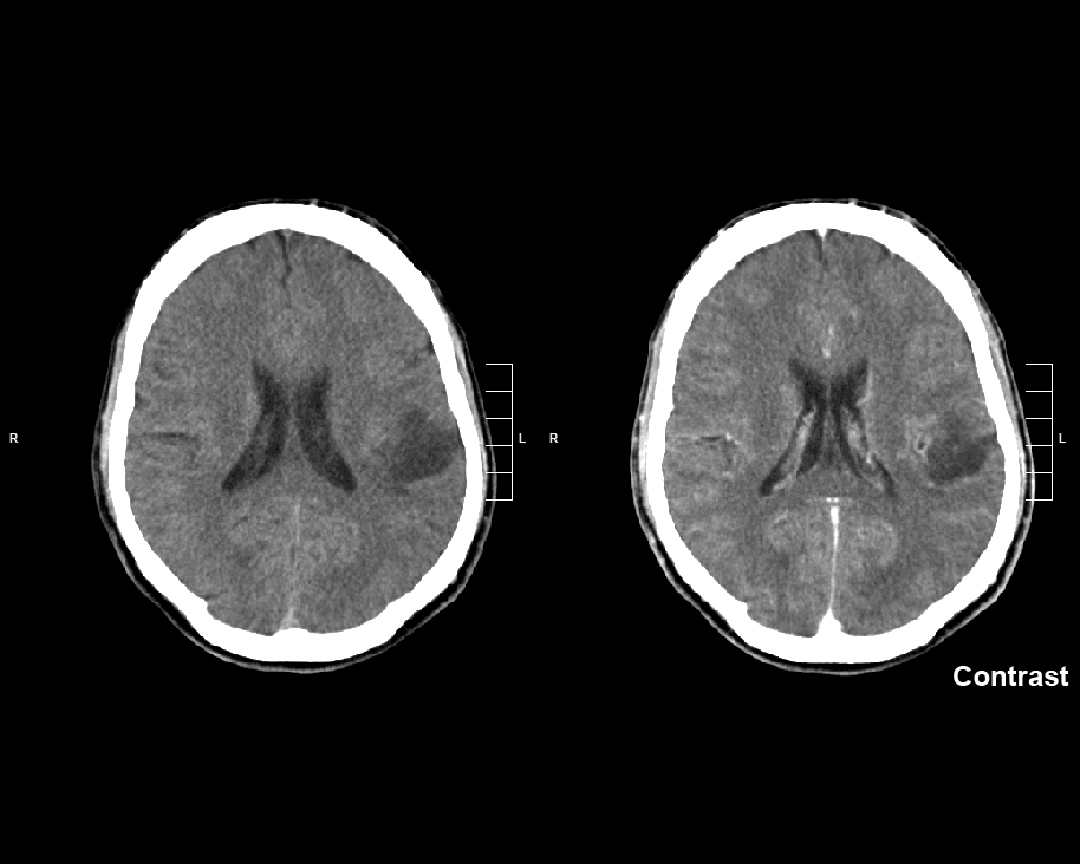

У «The New England Journal of Medicine» опубліковано результати подвійного сліпого дослідження 3-ї фази препарату ворасиденібу у пацієнтів з гліомою (Mellinghoff I.K. et al., 2023). Препарат ще не отримав регуляторного схвалення у США та ЄС і знаходиться на розгляді із статусом швидкого проходження (fast track) — у першому, та орфанного препарату (orphan medicine) — у другому випадку. Якщо регулятори ухвалять позитивне рішення, ворасиденіб може стати першою таргетною терапією гліоми низького ступеня злоякісності.

Згідно з опублікованими даними, лікування інгібітором IDH1/2 ворасиденібом (AG-881) знизило ризик прогресування або смерті на 61% порівняно з плацебо у пацієнтів з ізоцитратдегідрогеназа (IDH)-мутантною гліомою 2-го ступеня. Первинною кінцевою точкою було виживання без прогресування за даними сліпої оцінки, проведеної незалежним комітетом з огляду. Ключова вторинна кінцева точка — час до наступного протипухлинного втручання. Перехід на ворасиденіб з плацебо був дозволений після підтвердження прогресування захворювання за допомогою візуалізації. Одночасно з публікацією результати представлено на щорічній конференції Американського товариства клінічної онкології (American Society of Clinical Oncology — ASCO).